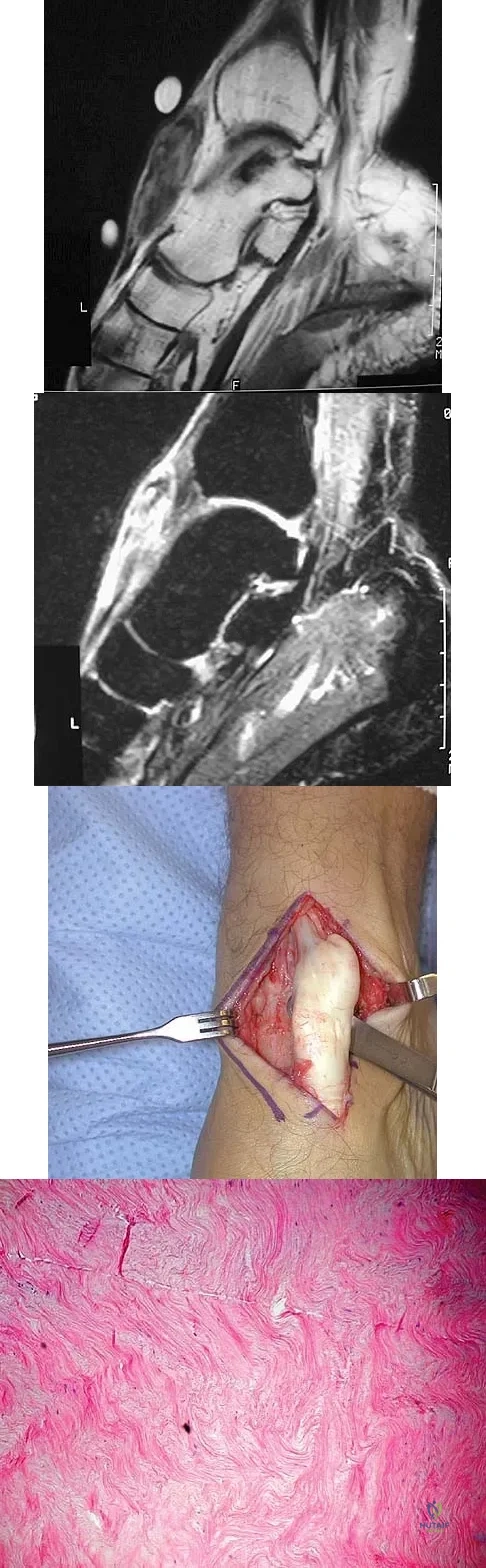

A 40-year-old man has a palpable mass over the dorsum of the ankle. He reports no history of direct trauma but notes that he sustained a laceration to the middle of his leg 6 weeks ago. Examination reveals a 4-cm x 1-cm mass. T1- and T2-weighted MRI scans are shown in Figures 12a and 12b. An intraoperative photograph and biopsy specimen are shown in Figures 12c and 12d. What is the most likely diagnosis?

Explanation